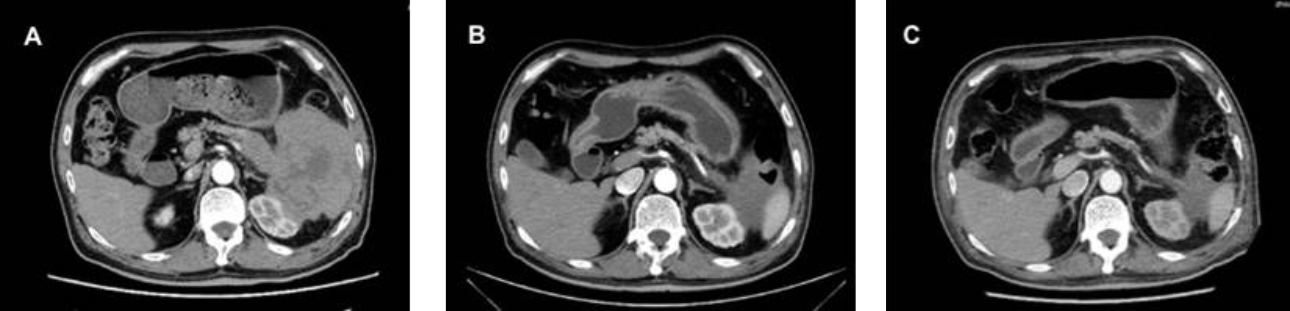

형상2: CT 검사에서 종괴 같은 연조직 밀도가 췌장 꼬리(pancreatic tail)부위 불분명한 경계, 비장(spleen)과의 경계와 명확하게 구분되지 않는 비장문(splenic hilum), 좌측 신장 그리고 다른 장기들 에서 확인됨. (Fig 2 A). 가벼운 단계에서 보통 단계로 진행된 종괴 (Fig 2 B-C). 비장(spleen), 좌측 신장 및 장관(intestinal tract) 일부의 종양 침윤이 관상면(coronal plane)에서 관찰됨. (Fig 2 D)